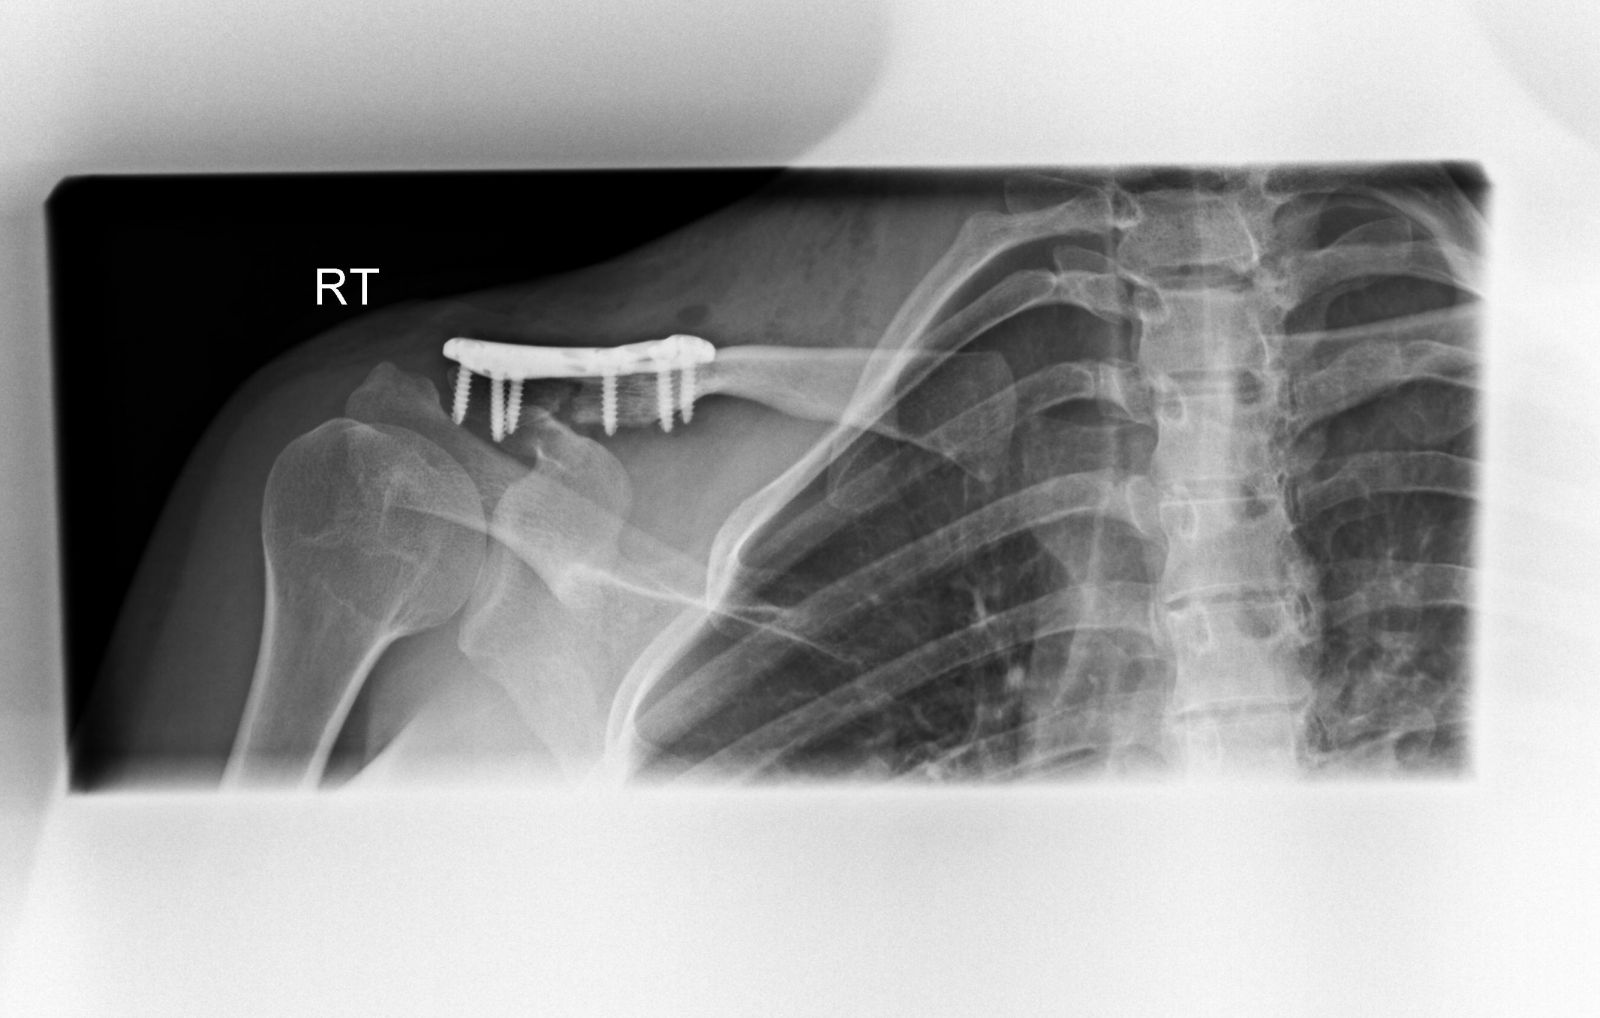

Μετεγχειρητικά, οστεοσύνθεση κατάγματος και αποκατάσταση κορακοκλειδικών συνδέσμων